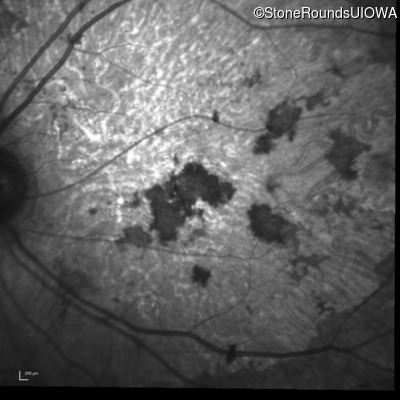

Infrared Fundus Photograph - Right - 20/200 sc

Exemplar